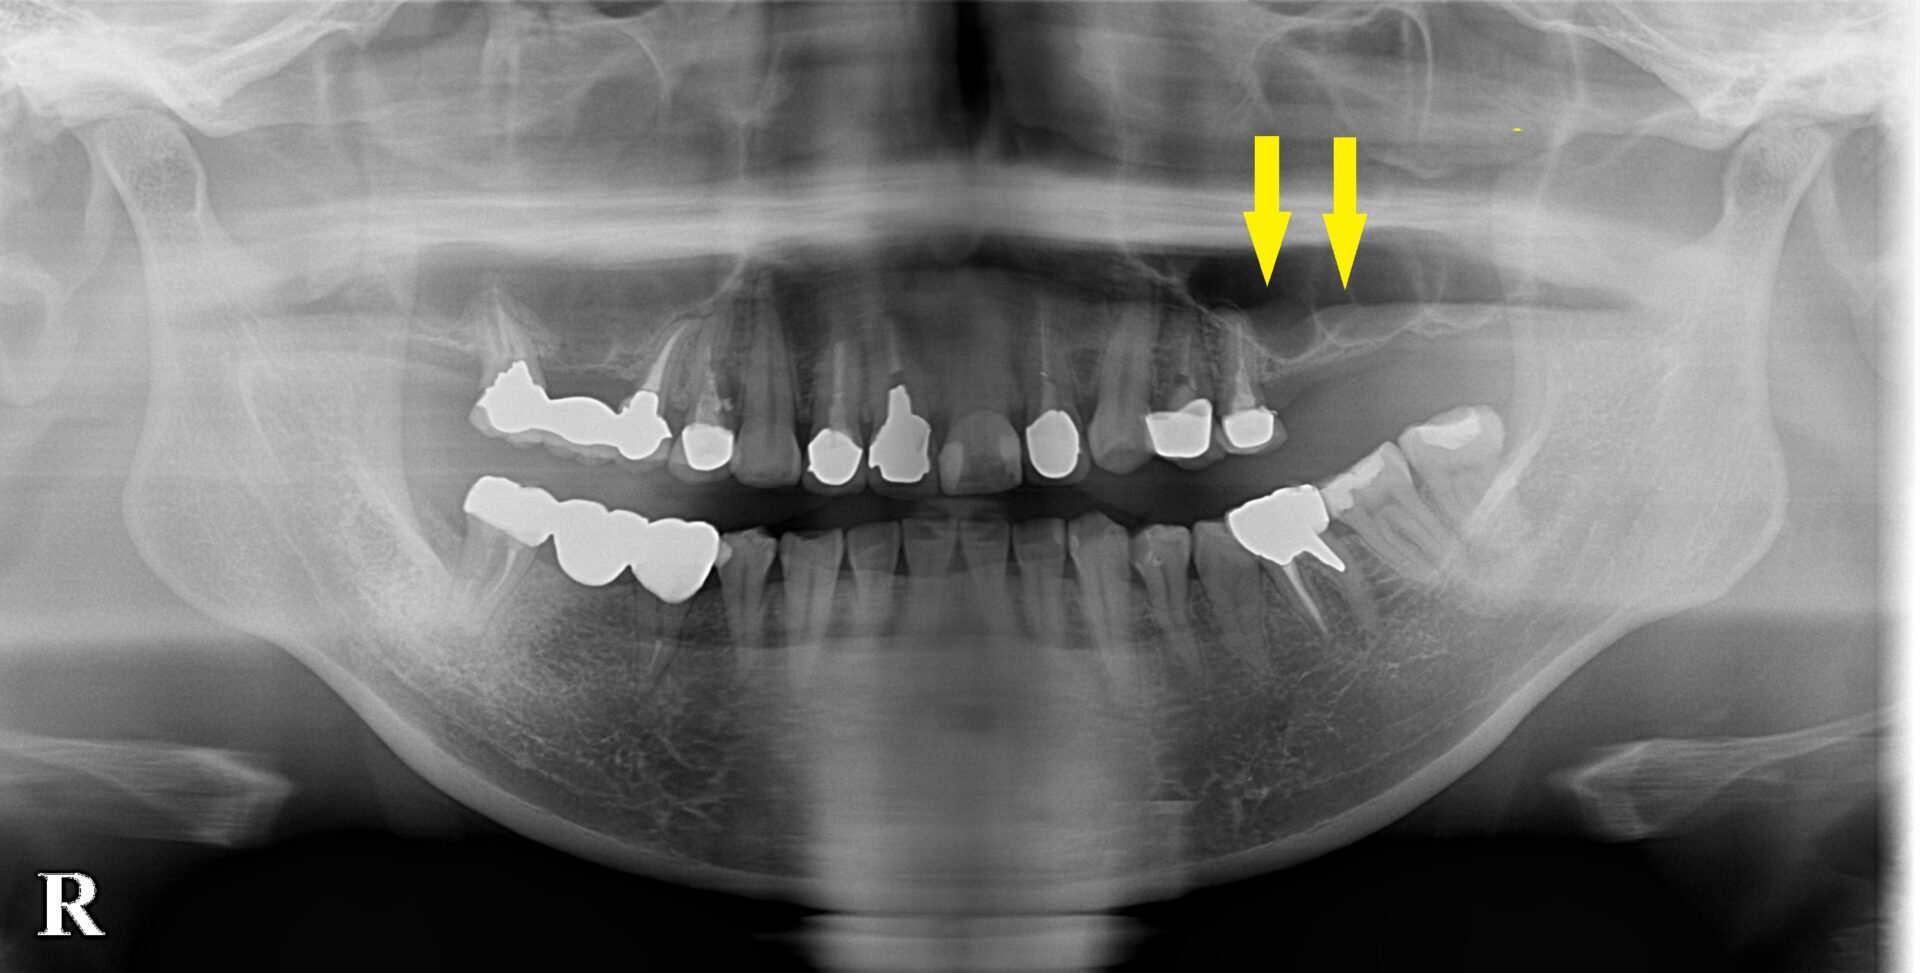

左の大臼歯2本が数年前に失われて、義歯を作ったのですが、どうにも使えず、インプラント治療を希望されたのですが、骨が薄くてできないと言われ、そのままになっていたそうです。

レントゲン、CTを撮影してみると、確かに骨は薄く、薄いところでは1mmあるかないかでした。

さらに骨の形態が複雑で、骨造成を行うにも、なかなかな難易度が高い状態でした。